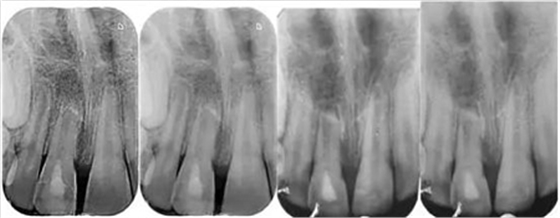

影像學(xué)檢查:根尖片以及全景片(圖2)提示牙槽骨骨折,根尖挫入至唇側(cè)骨板或鼻底。根尖片提示牙11,12 和21根尖發(fā)育不完全,呈喇叭口狀。受累牙的根管壁薄且不完全成形(圖2)。牙片顯示沒有冠折和根折。

隨訪12個月的X線記錄顯示:在年輕恒切牙的根管壁上有硬組織沉積。從長度上看,牙根并沒有繼續(xù)發(fā)育,但根尖處硬組織沉積,而且?guī)缀蹰]合了(圖 8)。

12個月后,對牙11進(jìn)行活力測試表現(xiàn)出輕微的陽性反應(yīng),建議繼續(xù)觀察看看血運(yùn)重建是否成功。熱/冷敏試驗(yàn)和電活力測試顯示均為陰性,表明牙髓神經(jīng)沒有再生。然而,只有在牙齒出現(xiàn)臨床上或影像學(xué)提示發(fā)生感染的情況下,才需要進(jìn)行根管治療。此外,牙齒變色和透明度改變的問題沒有得到改善,這會影響美觀,需要將來進(jìn)行干預(yù)。

牙12 顯示根尖完全閉合,牙髓活力測試陽性,提示已成功恢復(fù)。